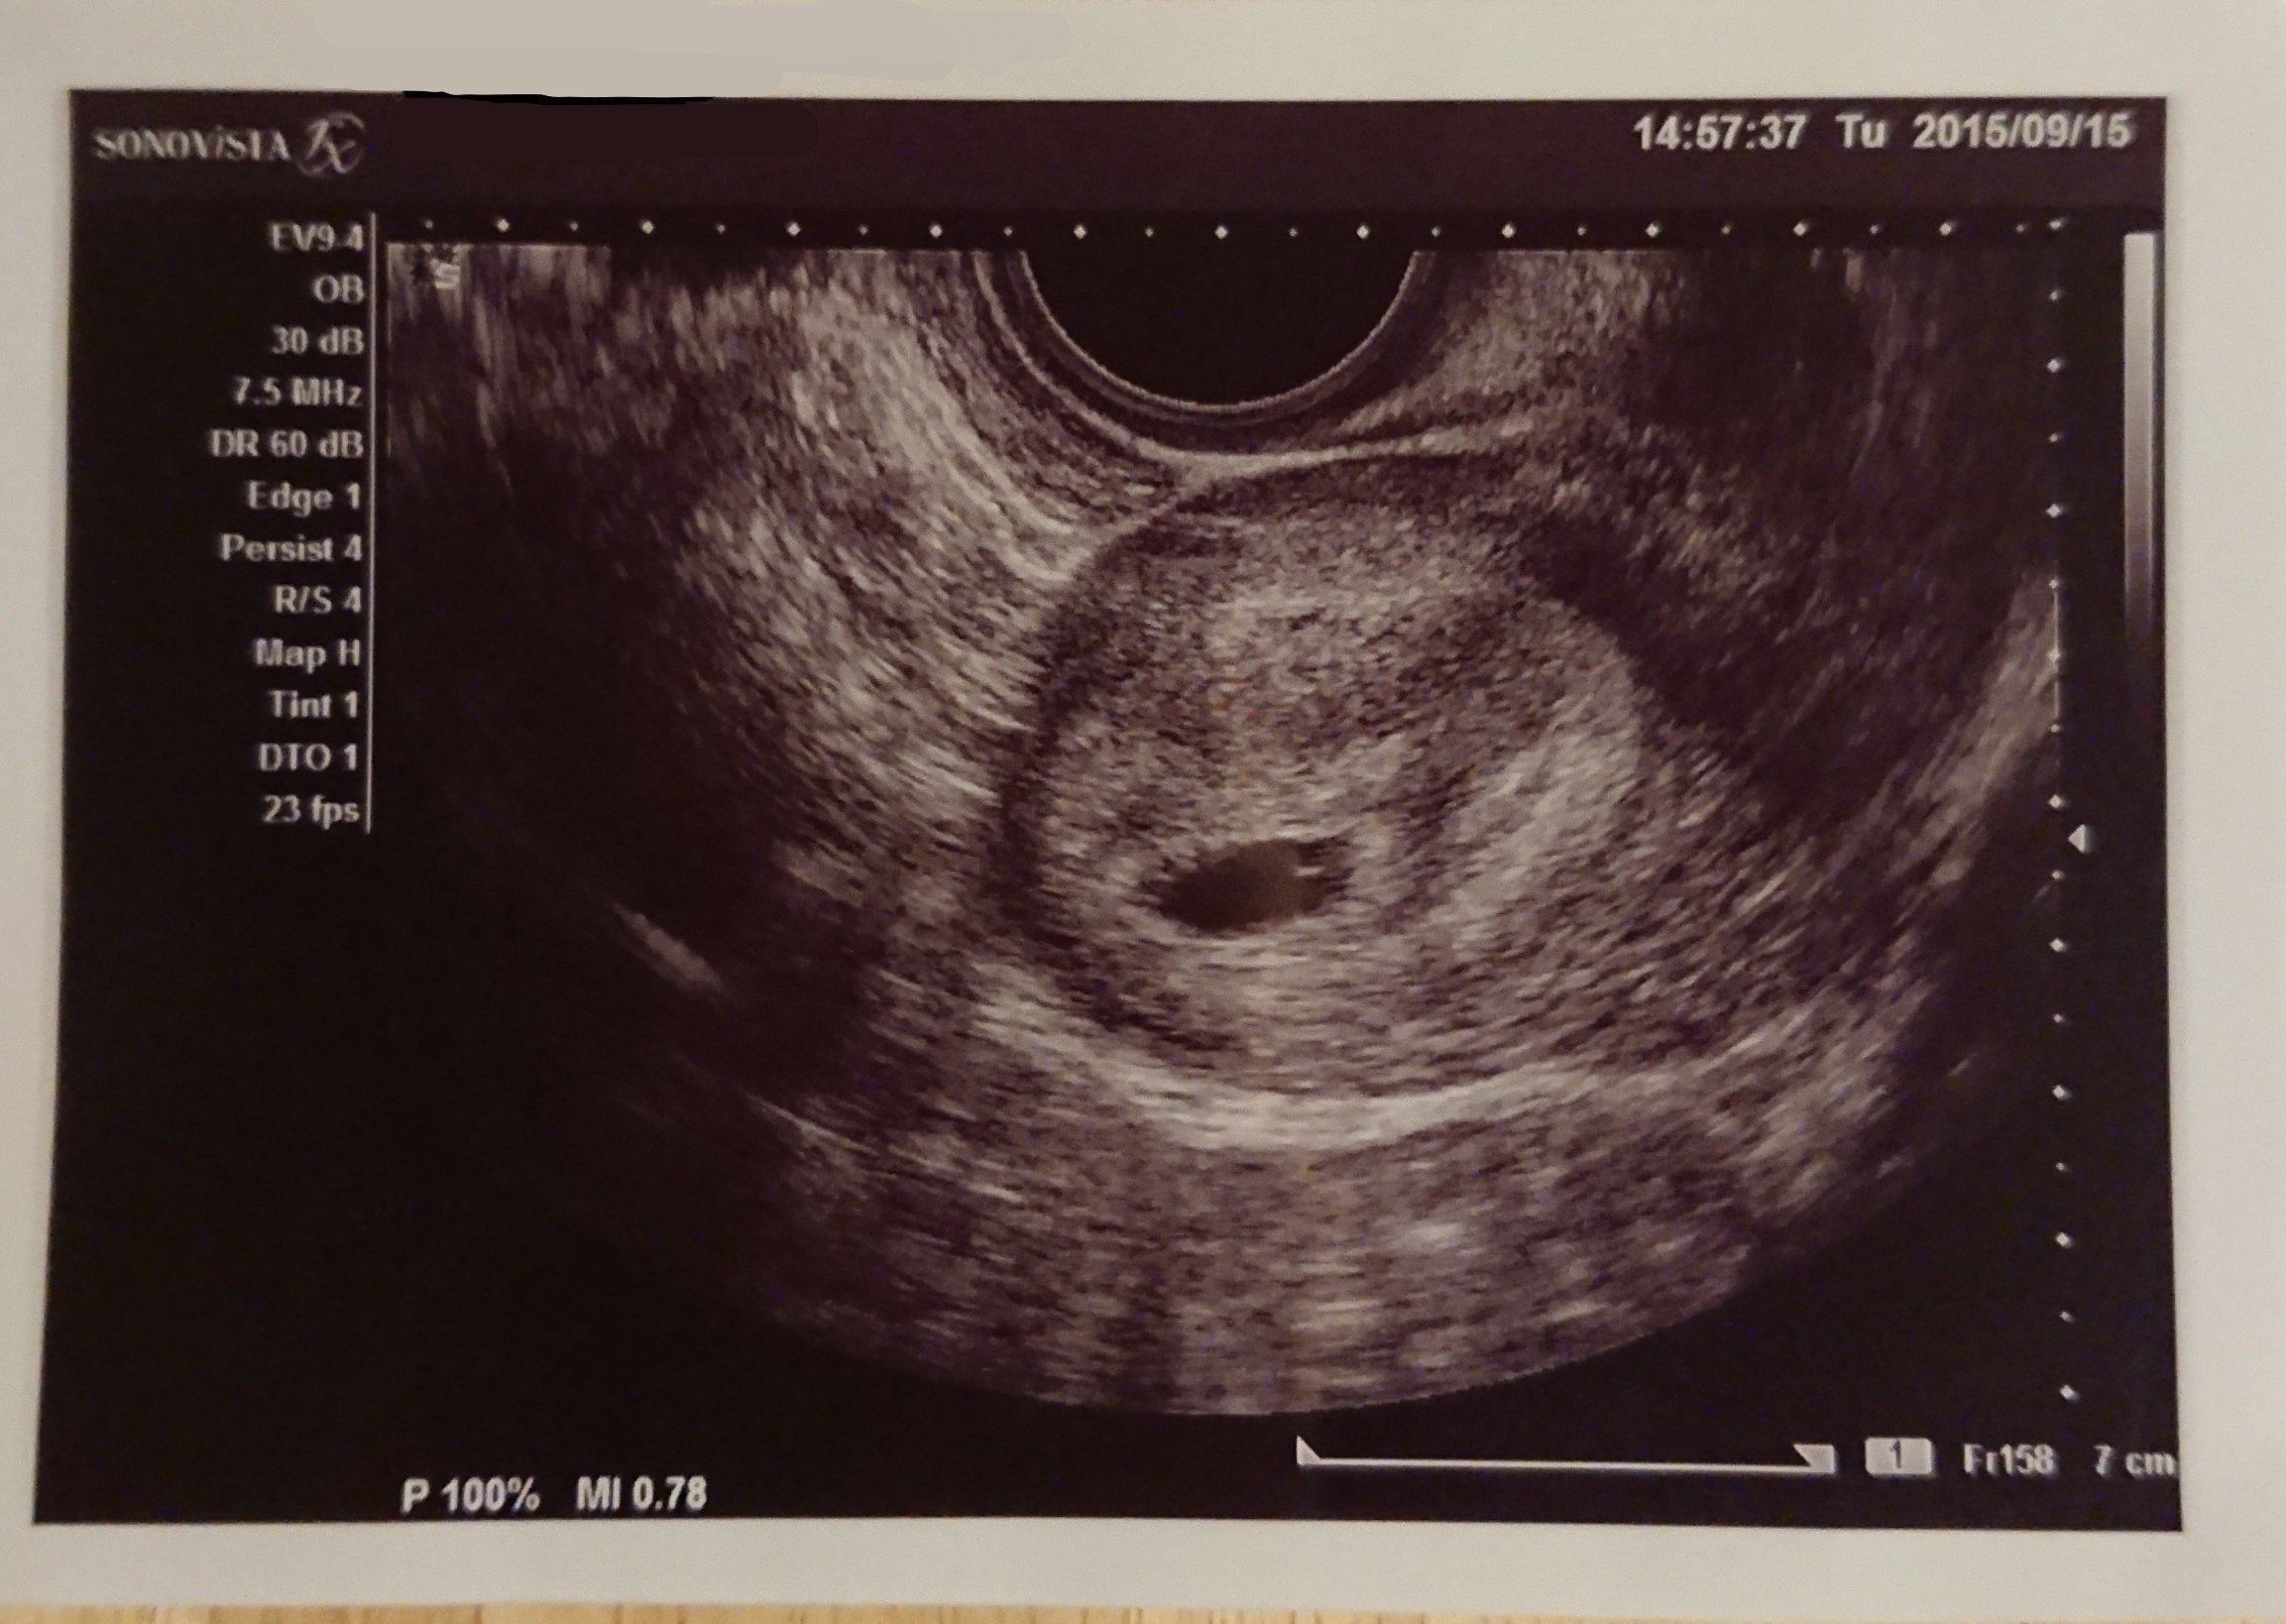

妊娠5週目 胎嚢を確認!

妊娠検査薬で陽性反応が出てから1週間後、産婦人科を受診し、初めてのエコーで胎嚢を確認しました。この時すでにつわりが始まっていたので常にムカムカしている状態です。